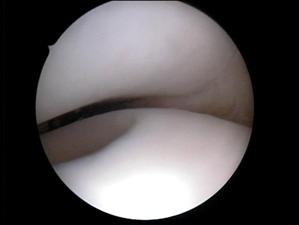

1.3. Diagnosticul Artroscopic al leziunilor cartilajului articular

Examinarea artroscopica a genunchiului ramine standardul de aur in diagnosticarea si evaluarea leziunilor cartilajului articular. Examenul artroscopic permite evaluarea suprafetei cartilajului, a rezistentei la presiune, dar mai ales a marimii si profunzimii zonei leziunii condrale. Numeroase sisteme de clasificare a leziunilor cartilajului articular au la baza examinarea artroscopica directa a acestuia (vezi capitolul 2).

Examinarea artroscopica a cartilajului permite evaluarea mai multor caracteristici ale acestuia. Rezistenta cartilajului la presiune se efectueaza cu ajutorul exploratorului (probe), si se refera la forta cu care acesta este impins inapoi dupa ce presiune a incetat. Persistenta unei depresiuni condrale este semn de "inmuiere" a cartilajului. Artroscopic se evalueaza si culoarea cartilajului care normal este alba, lucioasa, cu usoara tenta galbuie. Cartilajul artrozic are o culoare galbuie marcata, este mat.

La examinarea artroscopica suprafata cartilajului este neteda, lucioasa, o fara discontinuitati. Pierderea luciului, prezenta unor depresiuni, fisuri, fibrilatii, delaminari sint semne de leziune. De asemenea, o zona de ingrosare a cartilajului, depresibila la examinarea cu exploratorul, este semnul unei leziuni profunde: "blister".

Fig. 1.14. Imagini artroscopice - leziuni osteocondrale stadiu IV A si B ICRS la nivelul condilului femural |